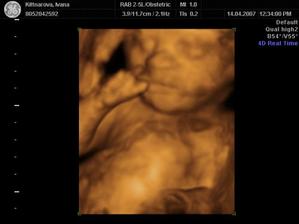

Někdy kolem 12. července by se nám mělo narodit naše první miminko. Všichni se už moc těšíme :o)

Podle ultrazvuku ve 20.tt by to měl být chlapeček.

Nakonec přišel Honzíček na svět už 2.7. 2007 v 11:15 císařským řezem. Měřil 50 cm a vážil 3320 g.